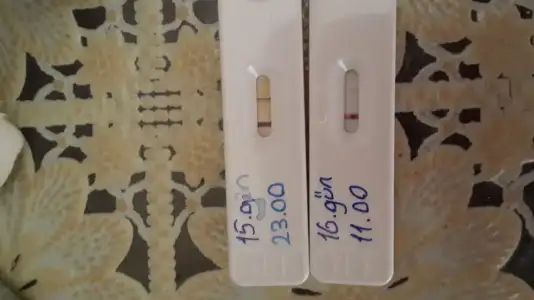

Aynen canim ya :)) hehehe nub fotosuda aticam yarin fikir olsunsibel canım çok sevindim RABBİM tamamına erdirsin hayırlısı ile sağ salim kucağımıza alalım inşallah. darısı diğer arkadaşlarında başına inşallah. seninde dediğin gibi bebeğin önce sağda kese sonra tavana yapışmış